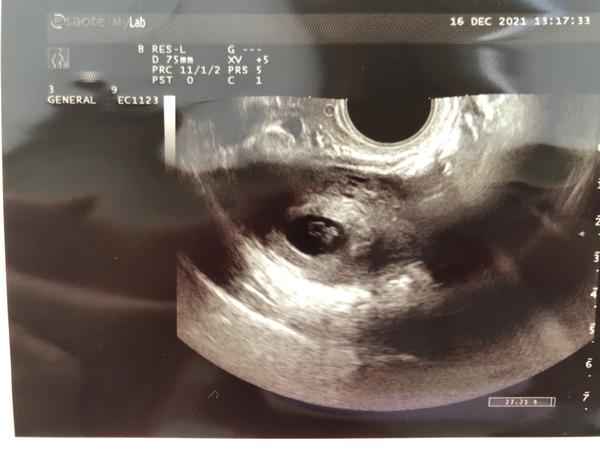

@ivuskake ja som mala v 7tt + 0 veľkosť plodu 0,87 cm a bilo srdiecko

@ivuskake toto je 7+2